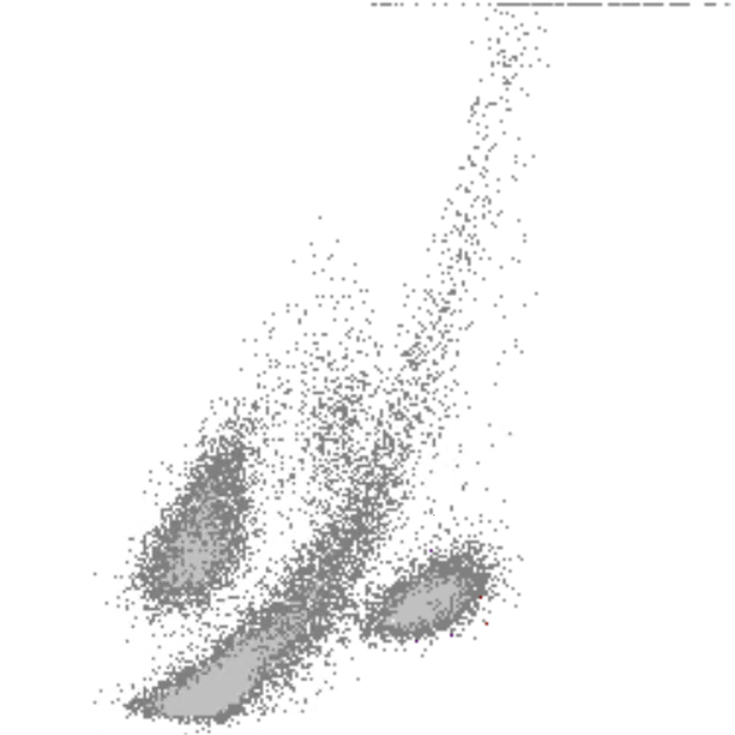

FSC scatter

FSC faible

FSC élevé